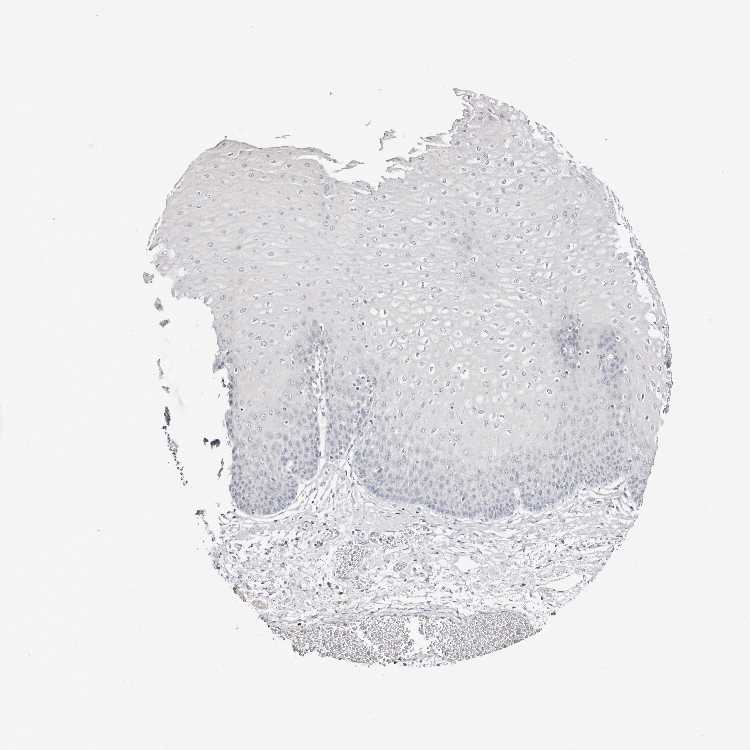

ESOPHAGUS - Antibody stainingi

Antibody staining in the annotated cell types in the current human tissue is reported as not detected, low, medium, or high, based on conventional immunohistochemistry profiling in selected tissues. This score is based on the combination of the staining intensity and fraction of stained cells.

Each image is clickable and will lead to virtual microscopy that enables deeper exploration of all samples and also displays staining intensity scores, fraction scores and subcellular localization as well as patient and tissue information for each sample.

Antibody HPA029725Antibody HPA055572Antibody CAB070192

Squamous epithelial cells Not detectedLowNot detected